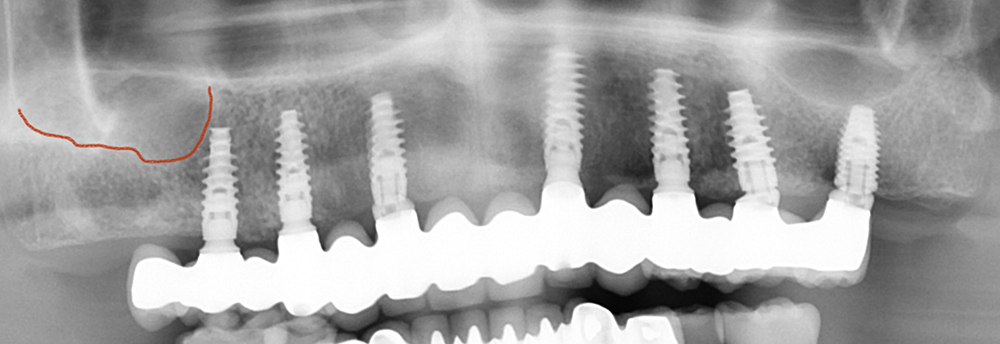

La radiographie panoramique montre les 7 implants en place. A droite (gauche sur photo) le dernier implant est plus en avant qu'à gauche du fait de la présence du sinus (trait rouge). La dernière dent est "en extension".

7 implants ont été mis en place en vue d'un bridge complet transvissé

Ce bridge remplace les 14 dents manquantes. Il est en céramique sur infrastructure zircone. Il n'a pas été ici nécessaire de rajouter de la céramique rose aux collets